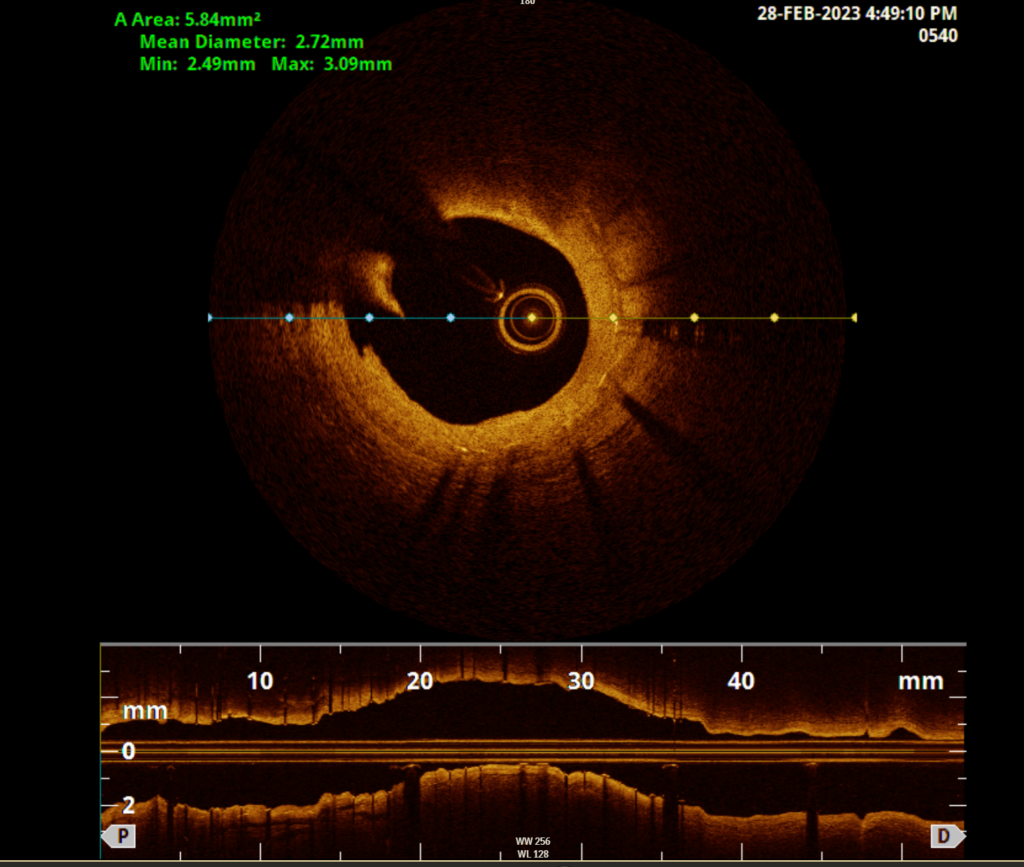

Um das Gefäß zu öffnen, schieben wir einen Katheter – in der Regel vom Handgelenk ausgehend, in einzelnen Fällen auch über die Leiste – im inneren der Hauptschlagader bis in das betroffene Herzkranzgefäß vor. Ist die Verengung im Röntgenbild lokalisiert, wird das Gefäß mit einem kleinen Ballon geweitet und durch einen Stent (Gefäßstütze in Röhrenform) offengehalten. Im Anschluss ist die Einnahme zweier Medikamente zur Verminderung der Blutplättchenaktivität für einen vom Arzt festgelegten Zeitraum notwendig.